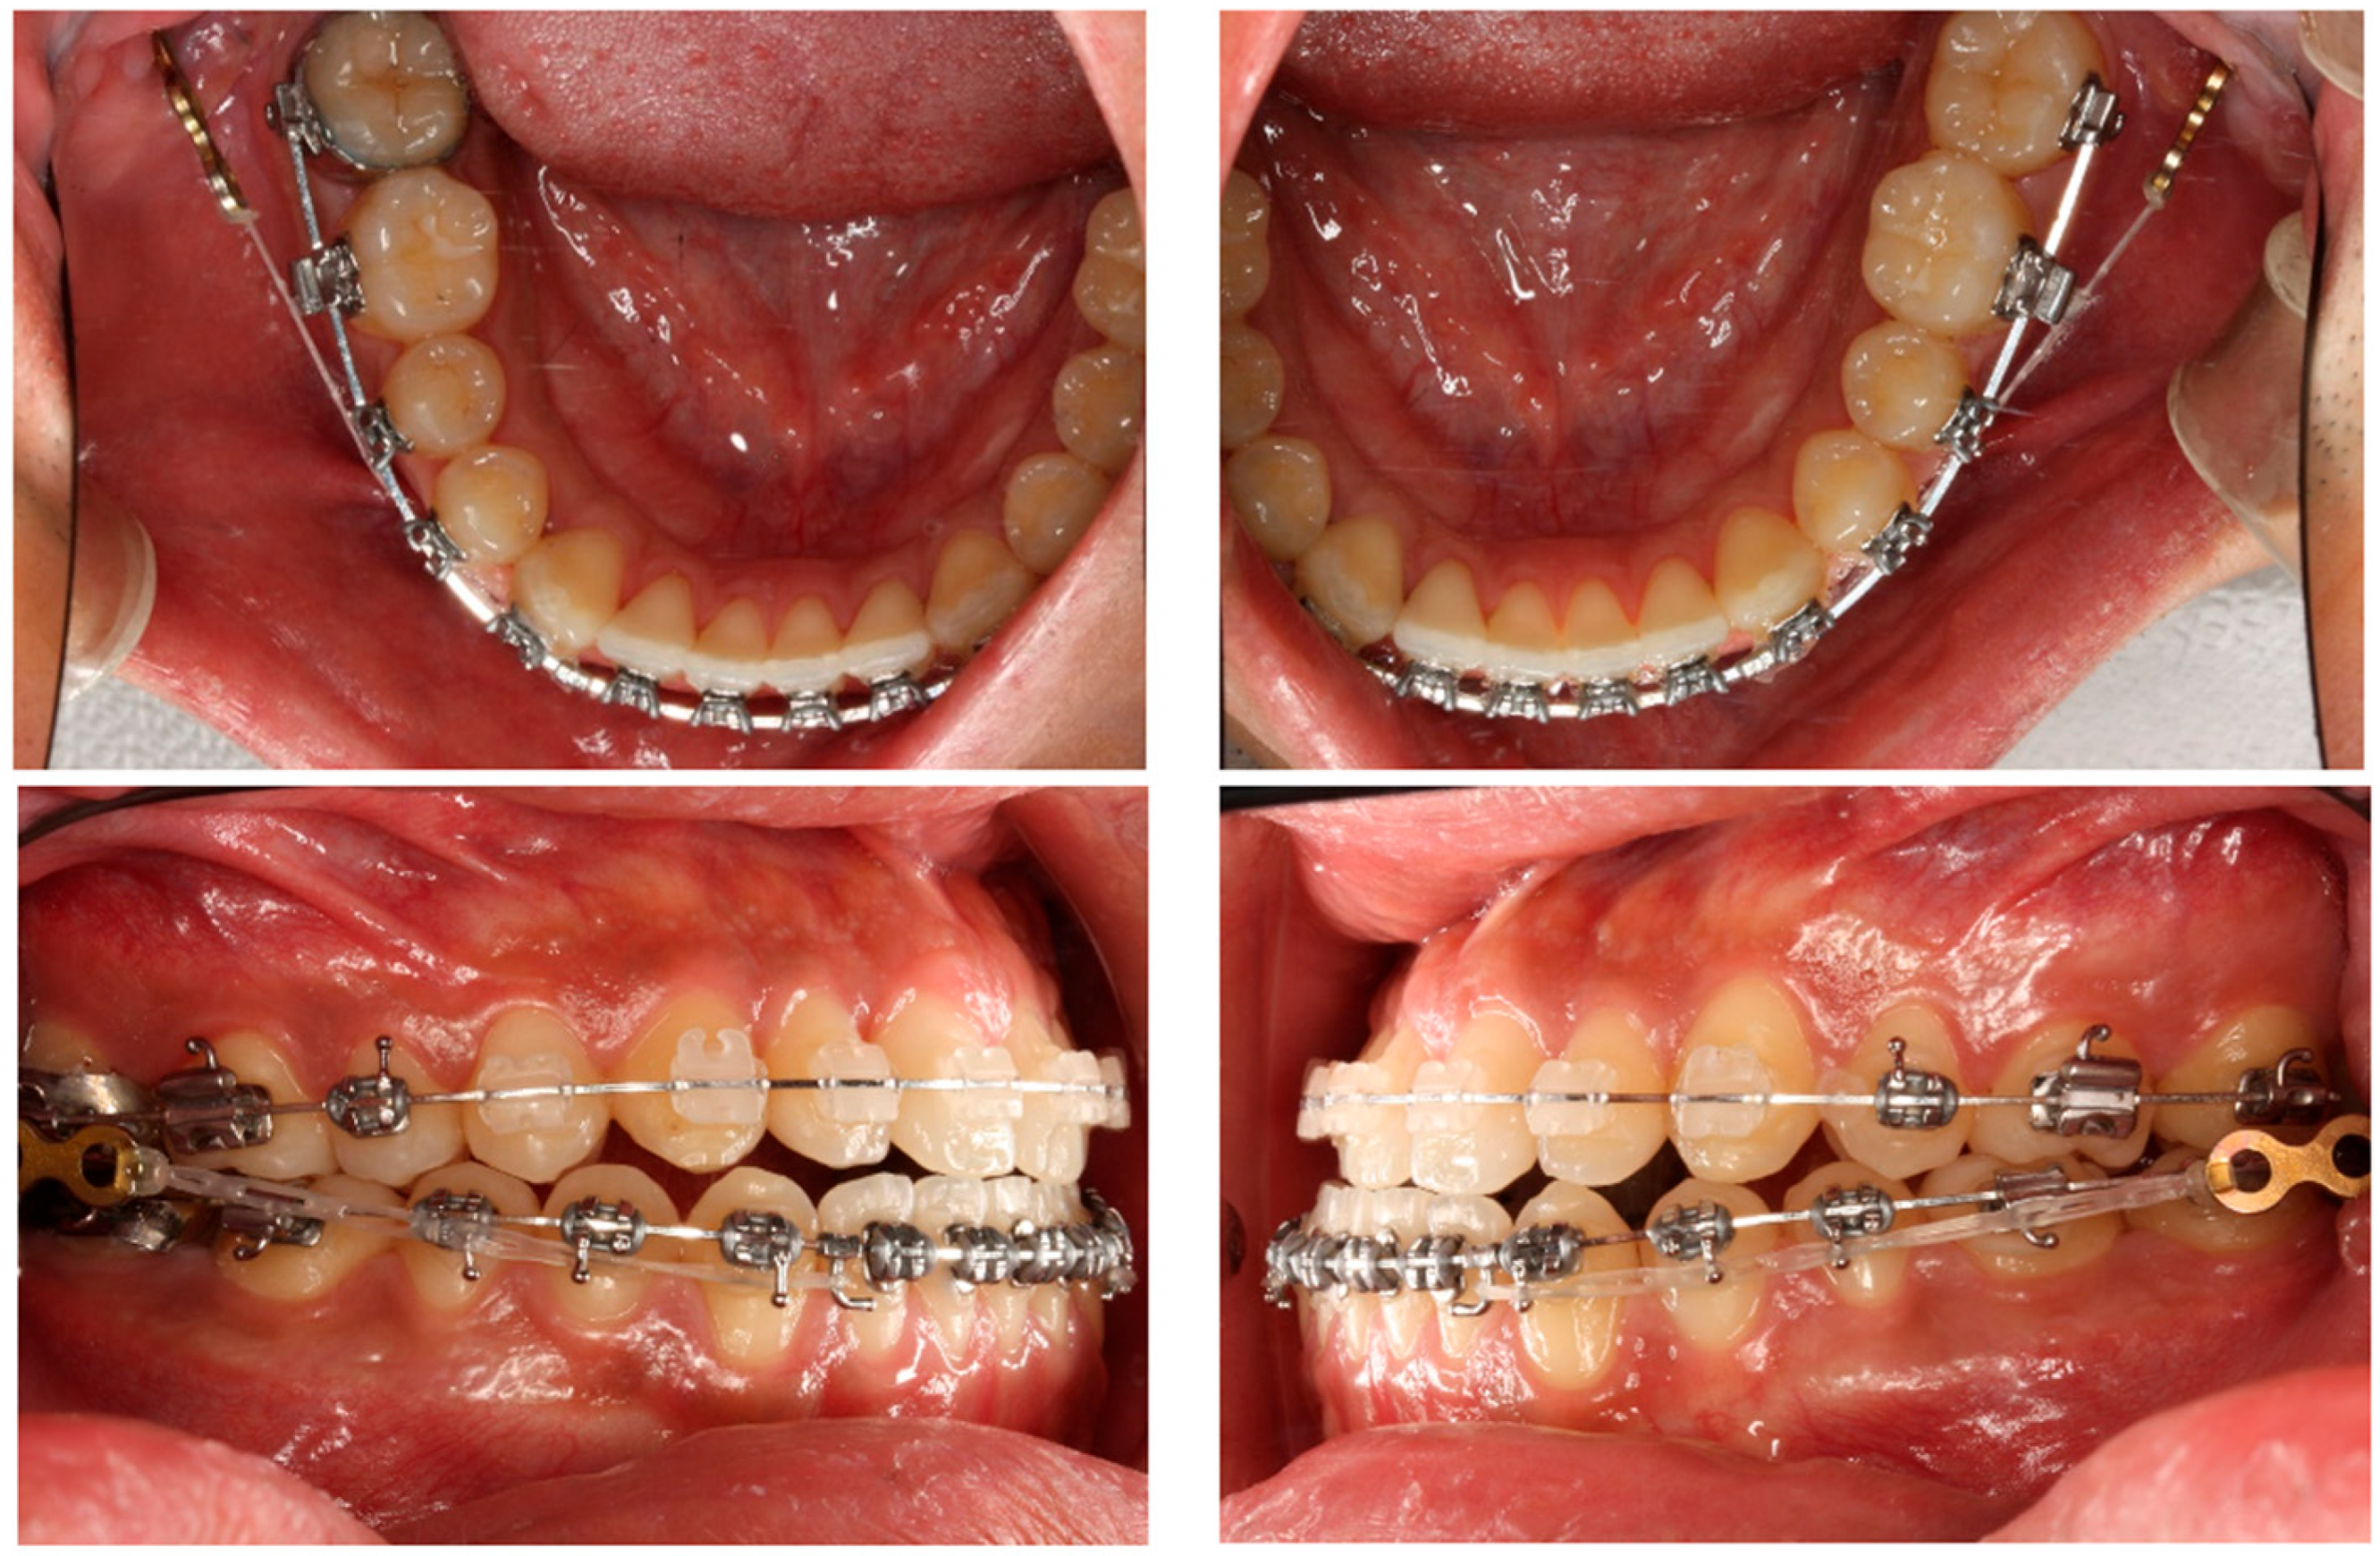

- Yu, J.; Park, J.H.; Bayome, M.; Kim, S.; Kook, Y.-A.; Kim, Y.; Kim, C.-H. Treatment effects of mandibular total arch distalization using a ramal plate. Korean J. Orthod. 2016, 46, 212–219. [Google Scholar] [CrossRef]

- Kook, Y.-A.; Park, J.H.; Bayome, M.; Kim, S.; Han, E.; Kim, C.H. Distalization of the mandibular dentition with a ramal plate for skeletal Class III malocclusion correction. Am. J. Orthod. Dentofac. Orthop. 2016, 150, 364–377. [Google Scholar] [CrossRef]

- Yeon, B.M.; Lee, N.-K.; Park, J.H.; Kim, J.M.; Kim, S.-H.; Kook, Y.-A. Comparison of treatment effects after total mandibular arch distalization with miniscrews vs ramal plates in patients with Class III malocclusion. Am. J. Orthod. Dentofac. Orthop. 2022, 161, 529–536. [Google Scholar] [CrossRef] [PubMed]